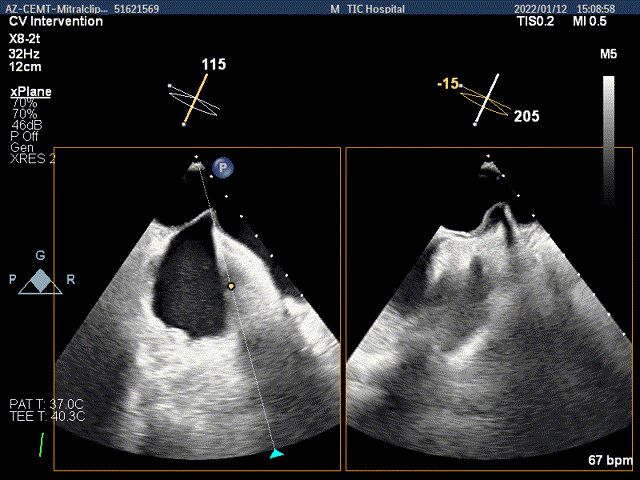

x-plane验证前后叶抓捕后bond明显

x-plane验证前后叶抓捕后跳跃征明显

3D-view验证两个夹子位置稳定,排列紧密